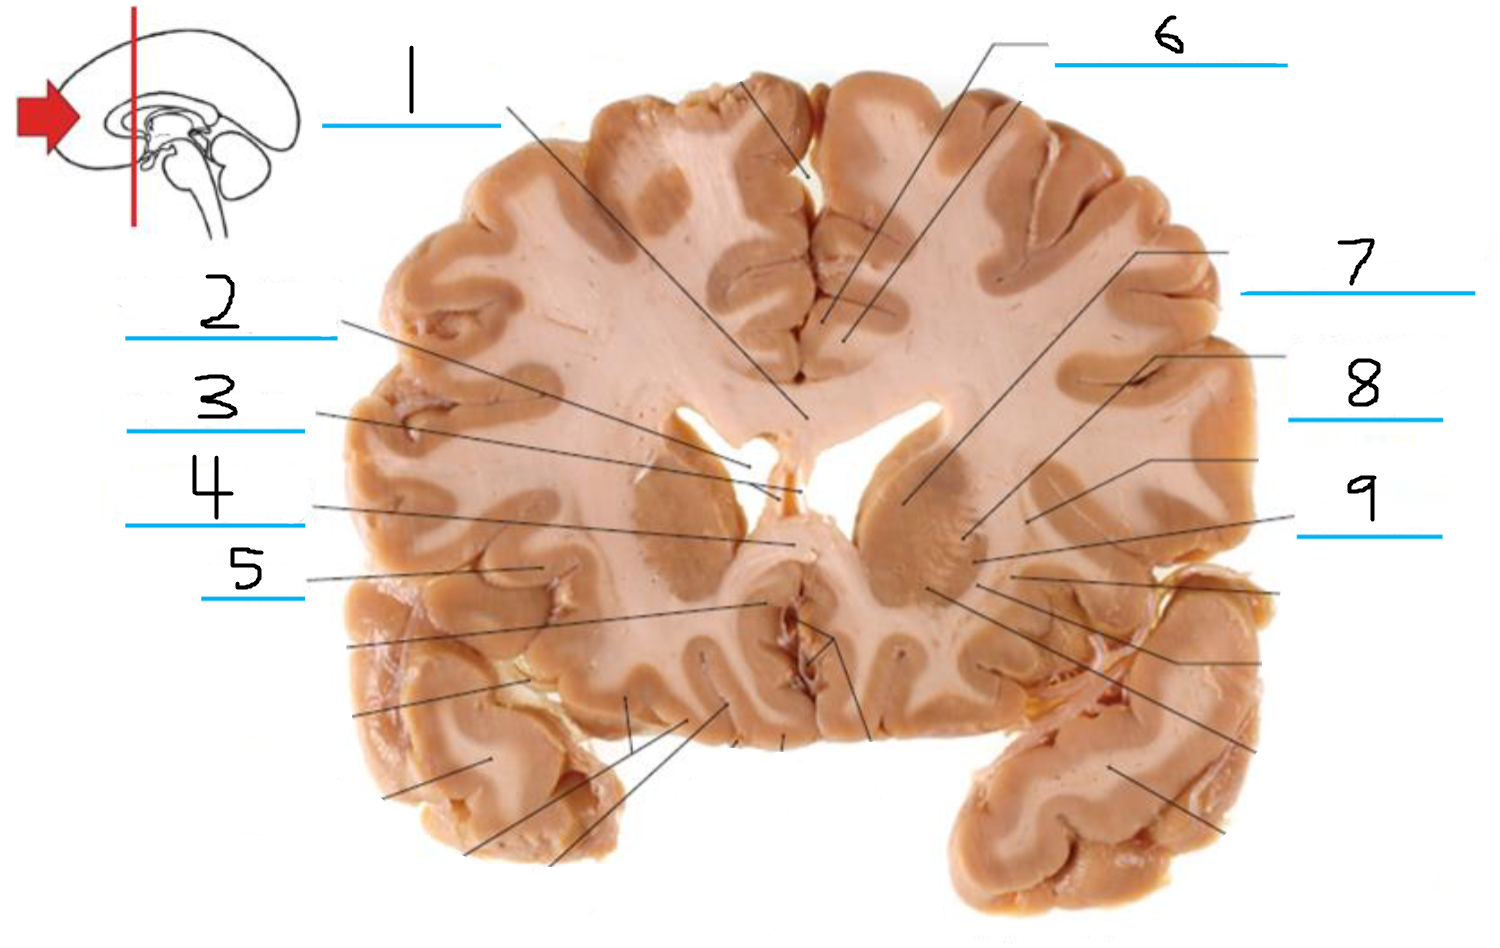

#1 is the:

Corpus Callosum

#2 is the:

Septum Pellucidum

#3 is the:

Lateral Ventricle

#4 and #9 is the:

Globus Pallidus

#5 is the:

Insula

#6 and #8 is the:

Anterior Commissure

#7 is the:

Optic Chiasm

#10 is the:

Putamen

#11 is the:

Internal Capsule

#12 is the:

Caudate